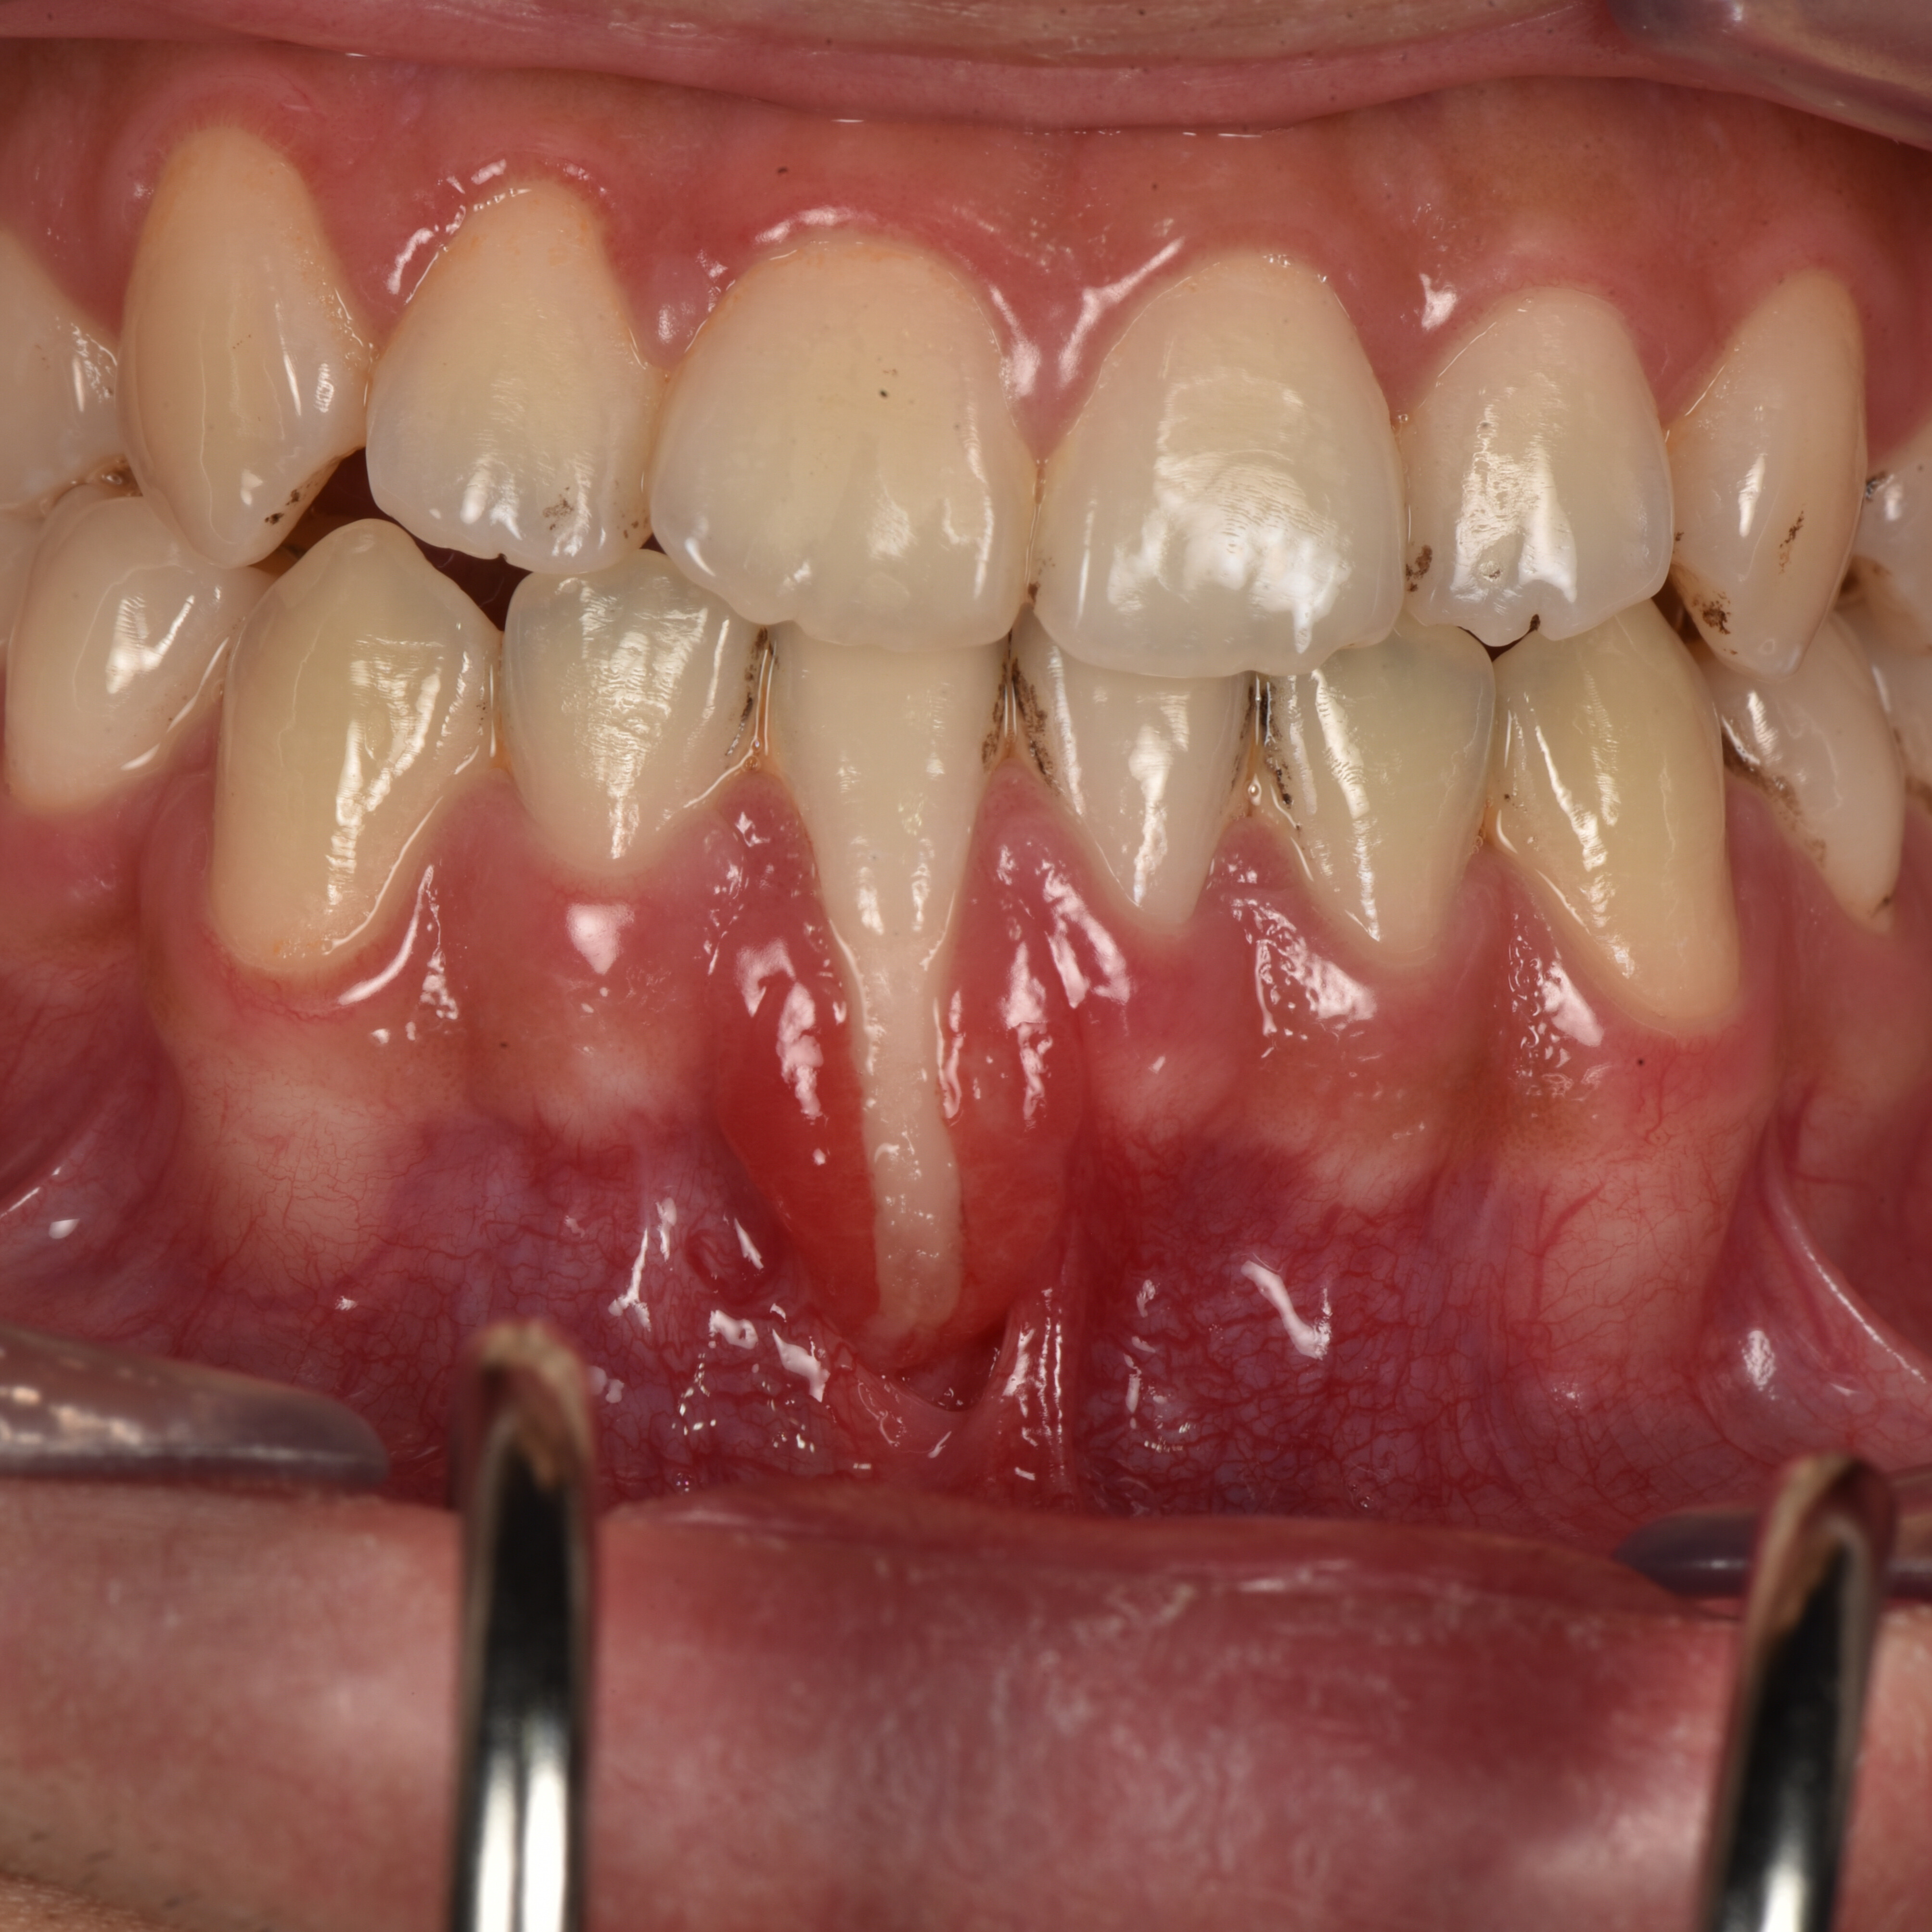

Điều trị tụt nướu- Viêm nha chu

Tụt nướu có thể dẫn đến nhiều vấn đề nghiêm trọng nếu không được điều trị sớm.